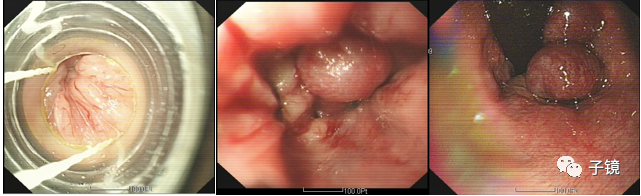

D、注意事项套扎部位充分注气,最好用CO2,以便暴露视野,首先选择病变最严重的部位进行治疗,一般在齿状线以上1~2cm套扎数目以每次1~3枚为宜错开平面同一水平面套点不要过多相邻部位最好稍微错开排便控制术前嘱病人排便,术后12小时内尽量避免排大便E、术后并发症及处理术后出血多能自愈,大量出血少见术后肛门坠胀:最常见,平卧休息约30min、坐浴、口服止痛剂;术后肛门疼痛:多可耐受,必要时止痛;术后感染:罕见致死性感染风险,酌情使用抗生素;外痔血栓形成:发生率为2%~3%,可予止痛、坐浴、手术刀挑破取出或切除血栓胶圈滑脱或断裂:选用高质量的胶圈,术后常规予通便药物,可在首次治疗后3~4周后重复套扎;溃疡形成:罕见,局部药物外用、坐浴理疗以及止痛药物。

2)套扎部位合理选择一般在齿状线以上1~2cm,交叉位套扎套扎数目避免密集以每次1~3枚为宜,以免术后肛门狭窄。